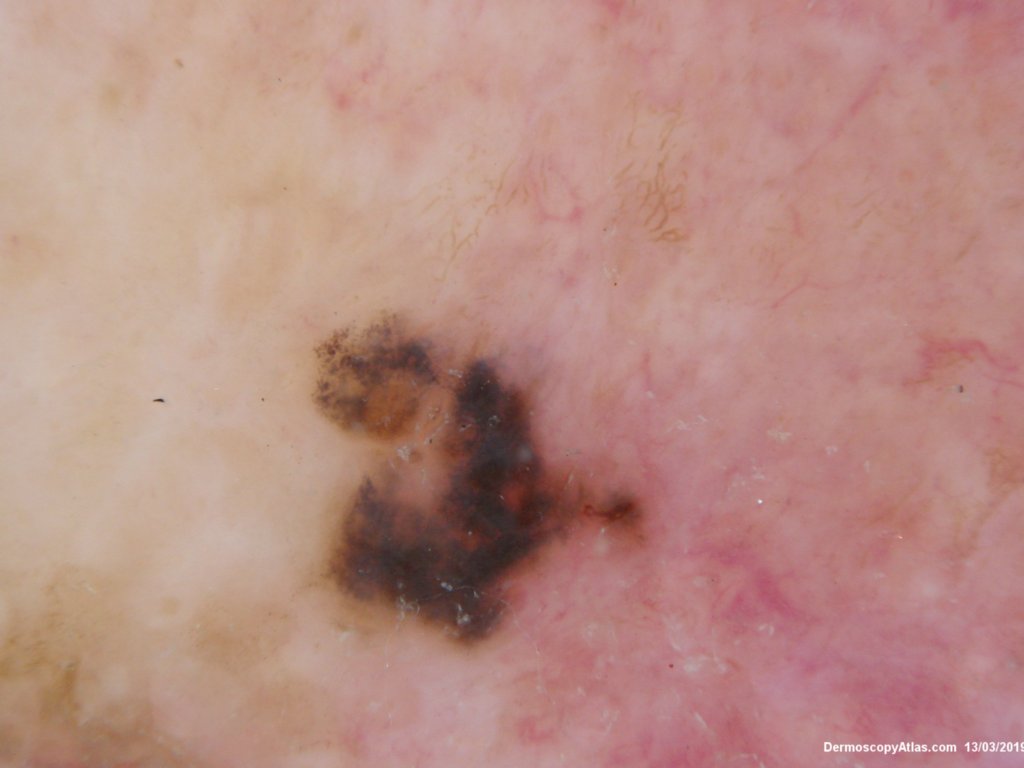

Description: Pigmented lesion on pinna

This lesion was noted on the ear during a routine skin check. Patient was not aware of it. The dermatoscopy showed an irregular blue black structureless lesion with some peripheral grey dots as peppering, an excentric area of regression and some white clods.